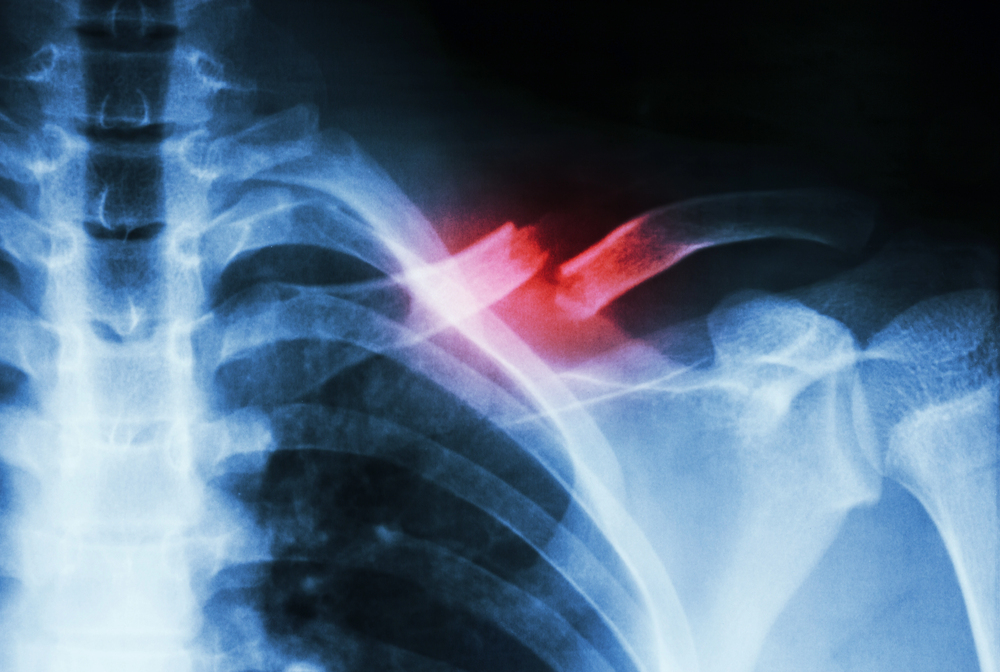

Types of Fractures in Nursing Homes and Assisted Living Facilities

Bone fractures in elderly patients can vary significantly, depending on the location, cause, and severity of the injury.

Traumatic fractures result from significant external force or trauma, such as falls, collisions, or physical abuse within care facilities. These fractures frequently affect the hips, pelvis, wrists, arms, and femur. A traumatic fracture can indicate serious underlying issues like lack of proper supervision, failure to implement fall prevention measures, or unsafe environmental conditions.

- Fractured vertebrae and spinal injuries